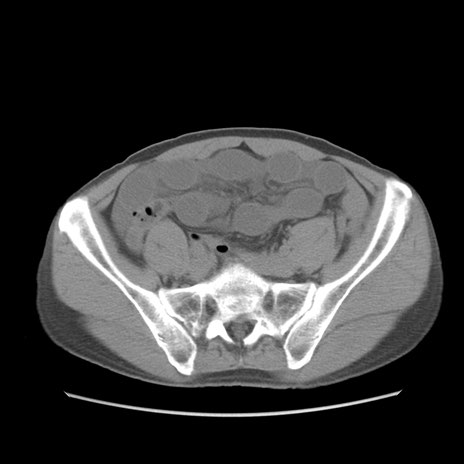

症例56 CT(横断像)

脂肪ウインドウ